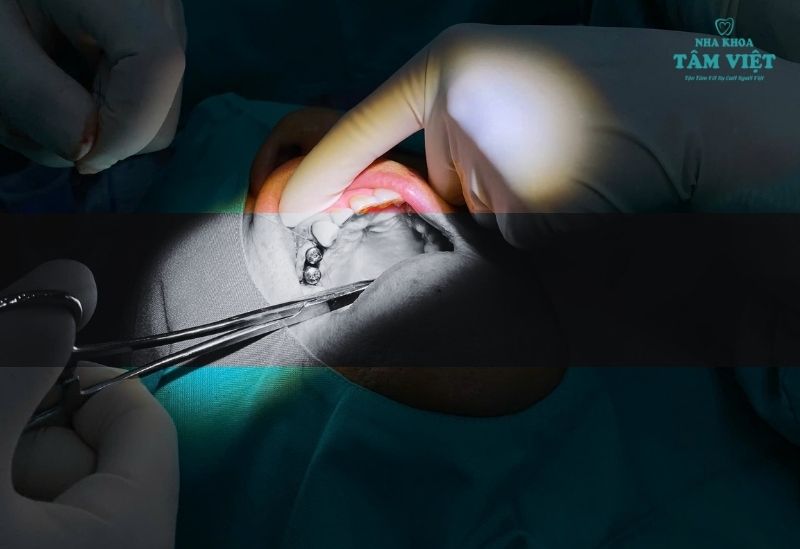

Đội ngũ bác sĩ của chúng tôi giàu kinh nghiệm, chuyên sâu về cấy ghép Implant và đã thực hiện thành công hàng ngàn ca phức tạp. Toàn bộ quy trình được hỗ trợ bởi hệ thống trang thiết bị hiện đại như máy chụp phim CT Cone Beam 3D, đảm bảo an toàn và chính xác tuyệt đối. Chúng tôi cung cấp đa dạng các loại trụ Implant chính hãng từ Hàn Quốc, Mỹ, Thụy Sĩ, giúp bạn có nhiều lựa chọn phù hợp.